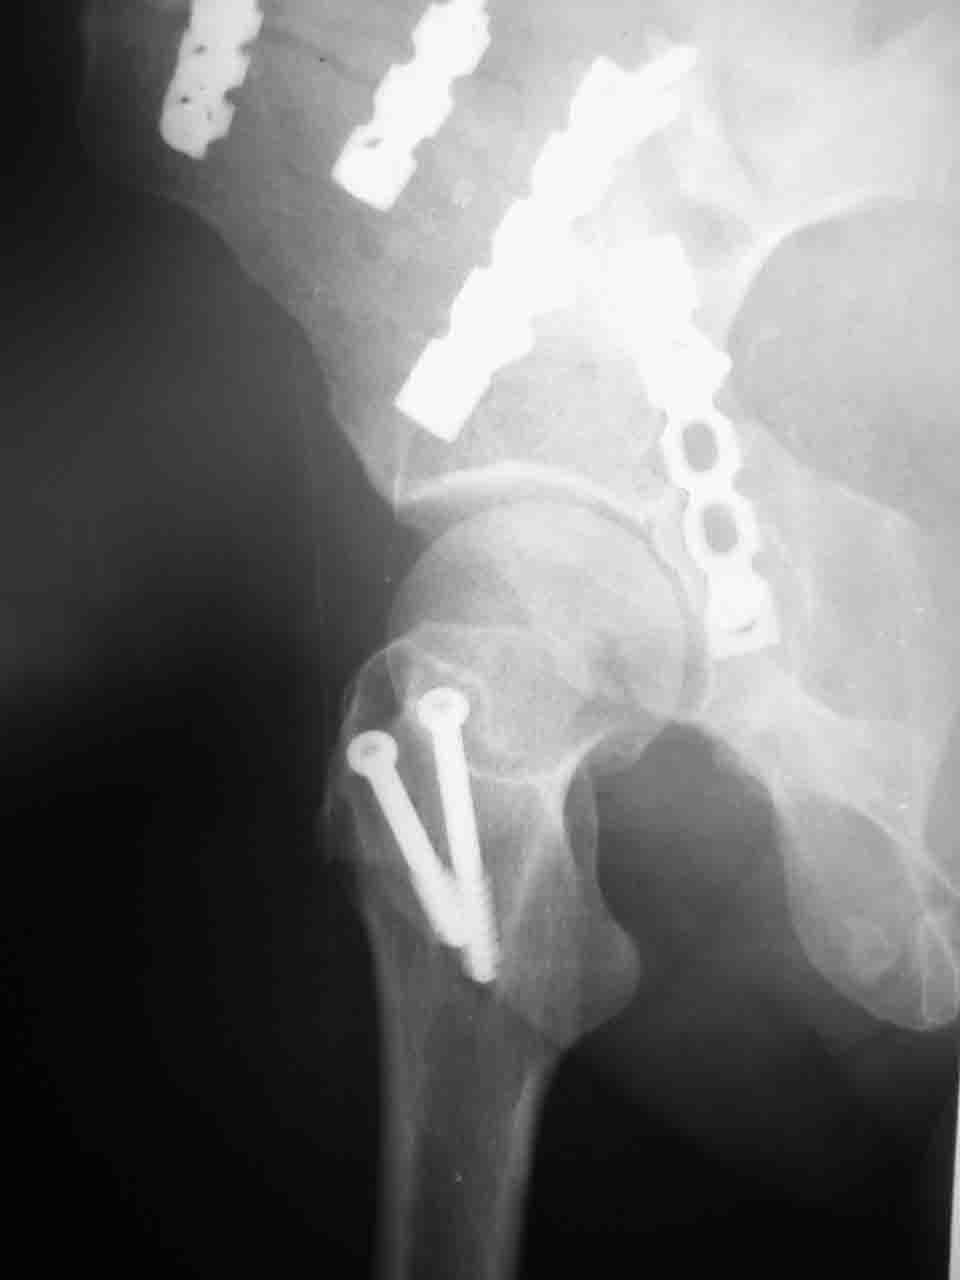

Интерес к реконструкции вертлужной впадины у меня появился довольно-таки давно, но до недавнего времени как-то не ощущалась готовность к практической реализации, а местный подход достаточно консервативен - перелом срастется,

а далее будет видно. Такую точку зрения я не разделяю, поэтому через конференции,ортофорум и свои случаи пытаюсь практически и теоретически *продвинуть* для себя тему реконструкции вертлужной впадины.

Логика подсказывает, что все-таки лучше иметь анатомически полноценную впадину, хотя ранее упоминалось состояние вторичной конгруэнтности и одно наблюдение у меня есть, когда у больного с полностью нарушенной анатомией впадины и подвывихом головки бедра кзади и кверху боли отсутствовали при относительно достаточном для стиля жизни больного объёме движений. Но это только одно наблюдение и кроме перелома впадины у этогобольного была и тяжелая ЧМТ в анамнезе. Основываясь на формулировке структуры ацетабулюм Э. Летурнеля - как перевернутой буквы Y, впадина для полноценной функции сустава должна иметь сферичность, соответствующую размеру головки бедра и если один из компонентов в дефиците, то функциональные последствия рано или поздно проявятся.

Сложностью, ассоциативностью характера перелома, я бы с радостью воспользовался мининвазивной перкутанной фиксацией винтами, но боюсь, что результат был бы ещё хуже, техникой непрямой репозиции перелома не владею, поэтому пытаясь получить анатомичную впадину приходится широко открывать, по крайней мере пока, а дальше буду пытаться уменьшать пространство...

Илеофеморальный доступ не совсем передний и сравнительно с илеоингвинальным, и Кохера-Лангенбека открывает весь наружный таз кроме самых передних отделов лонных костей, фиксацию которых я не ставил в задачу. Обширность диссекции, большая длительность операции и более высокий риск гетерооссификации - отрицательные моменты в обмен на возможность легче ориентироваться.